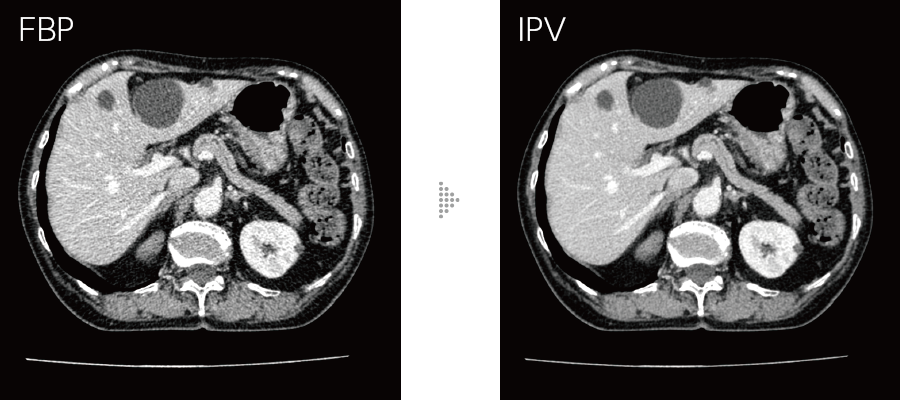

IPVはAI技術*4を活用して開発した画像再構成です。充分な反復処理により得られる画像を教師データとして処理を高速化。富士フイルムが開発したVisual Modelに基づき、RawDataを起点とした画像再構成処理により、NPS(Noise Power Spectrum)をFBP(Filtered Back Projection)に近づけ、高いノイズ低減率においても、画像の質感変化を抑えます。画像ノイズを最大90%*5低減し、被ばく量は最大83%*6低減。低コントラスト検出能を最大2倍*6に改善します。

統計学的モデル、オブジェクトモデル、物理学的モデルに基づき、画像ノイズや画質を繰り返し演算処理により制御する技術です。

高周波から低周波まで均等な割合でテクスチャを調整しながら視認性に影響を与えるノイズ周波数特性をFBPに近づけました。

- *5 腹部での場合

- *6 水ファントムに対してIPVの強度レベルStrong5を使用して画素値の標準偏差にて試験した場合